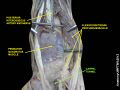

Wrist joint. Deep dissection.Anterior, palmar, view.